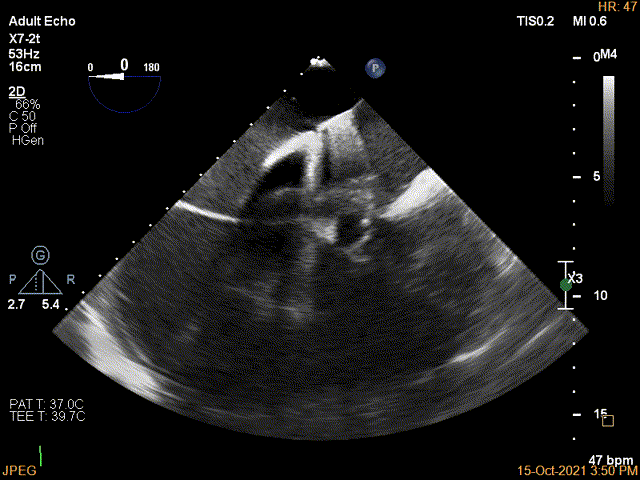

3D确认左房较大,穿刺点位近似于3点位

3D视图下大鞘位置及长度测量

2D视图下trajactiory